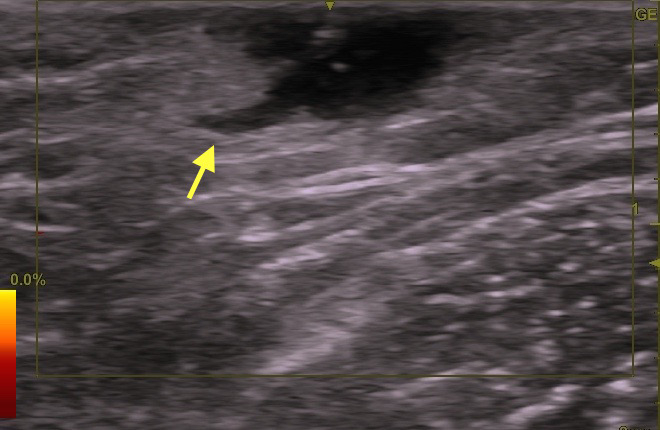

よってエコー(下写真)は必須でしょう。

検査所見の詳細は、過去のブログを参照してください:粉瘤腫の超音波検査